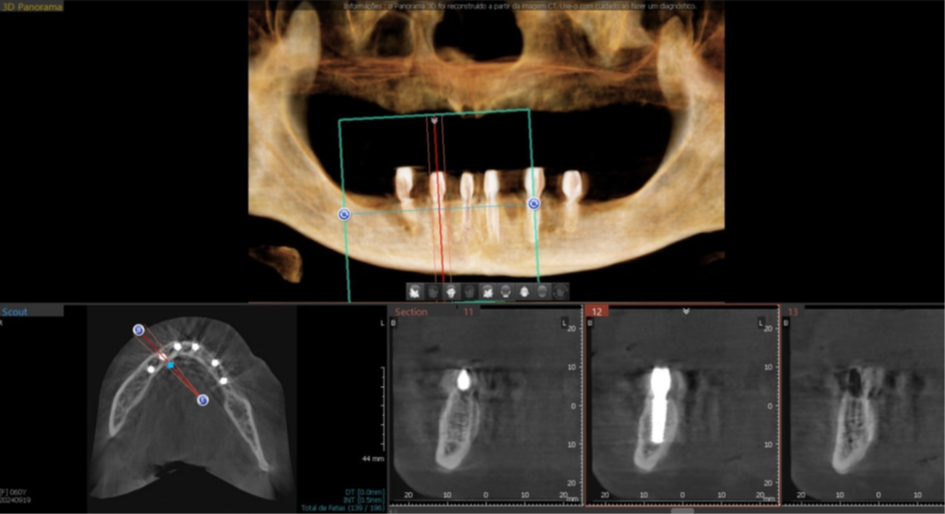

Foram planejados seis implantes nas seguintes medidas: elemento 31: 3.5x11mm; elemento 33: 3.5x11mm; elemento 35: 3.5x7mm; elemento 41: 3.5x11m; elemento 43: 3.5x11mm; elemento 45: 3.5x7mm; que foram distribuídos ao longo da mandíbula. O planejamento virtual do guia cirúrgico foi realizado em parceria com a empresa TechnoGuide, sendo posteriormente validado e aprovado para a confecção do guia definitivo.

Figura 8 – Planejamento digital do implante 31.

Figura 9 – Planejamento digital do implante 33.

Figura 10 – Planejamento digital do implante 35.

Figura 11 – Planejamento digital do implante 41.

Figura 12 – Planejamento digital do implante 43.

Figura 13 – Planejamento digital do implante 45.